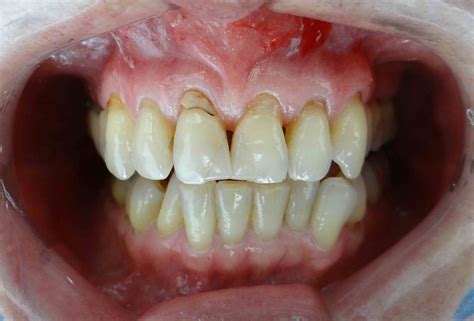

Las encías retraídas, también conocidas como recesión gingival, ocurren cuando el tejido que rodea los dientes se retira, revelando una mayor parte de la raíz del diente. Cuando hablamos de encías retraídas nos referimos a un desplazamiento del tejido gingival que provoca una sobreexposición del diente. Las encías se desplazan hacia arriba en los dientes superiores y hacia abajo en los dientes inferiores dejando al descubierto parte de la raíz dental. Esto no solo afecta a la estética, sino que también compromete la protección natural de los dientes, aumentando la sensibilidad y el riesgo de enfermedades.

El principal síntoma es el sangrado de la encía durante el cepillado. Si al mirarte al espejo notas que tus dientes se ven más de lo habitual o si experimentas sensibilidad al frío y al calor, puede que estés ante un problema muy común: las encías retraídas. La recesión gingival o encías retraídas son una de las patologías más comunes de salud dental, que debe ser tratado adecuadamente. Además, la propia retracción provoca que la raíz del diente se exponga, las encías retraídas también ocasionan un aumento de la sensibilidad dental. Otra de las consecuencias de las encías retraídas es el empeoramiento en el aspecto de la sonrisa.